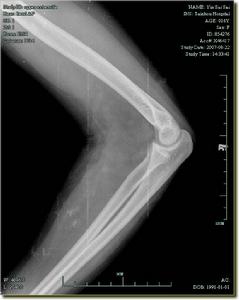

肱骨外髁骨折x片X線照片顯示肱骨小頭的骨折線多超過化骨核的1/2,或不通過小頭化骨核,而通過肱骨小頭與滑車間溝的軟骨在乾骺端處有一骨折線。骨折塊可向外側移位。骨折脫位型X線片,正位片顯示骨折塊連同尺橈骨可向橈側或尺側移位,側位片顯示可向後側移位,偶可見向前移位者。肱骨外髁骨折在X線片上表現為多種多樣,在同一骨折類型中表現也常不一。

肱骨外髁骨折外傷史,傷後肘部疼痛,腫脹,肘呈半屈曲位。肘外側局限性或廣泛壓痛,有骨擦感,成人X線可顯示骨折線及類型。